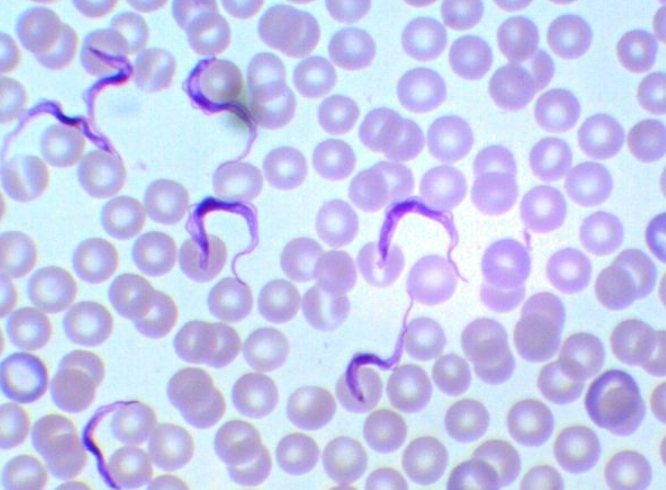

Trypanosoma spp.

Trypanosoma spp.